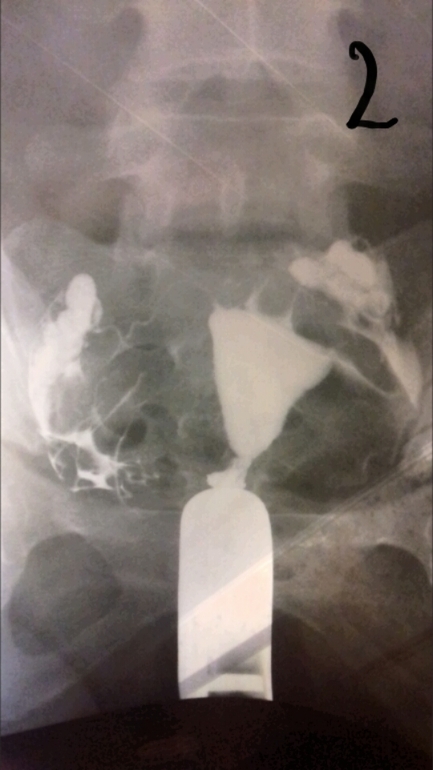

ГСГ помогите расшифровать.

ГСГ, ЭХО, МСГ, ФертилоскопияВсем привет. Кто понимает в снимках. Сделала гсг. На третьем сказали жидкость вышла, но как-то долго она выходила и спайки видно, поставили эндометриоз и спаечный процесс в брюшной полости. Беременность не наступает и стимуляции были. В 2006 году было кесарево и в 2012 прижигали эррозию ш/м, больше ничего.